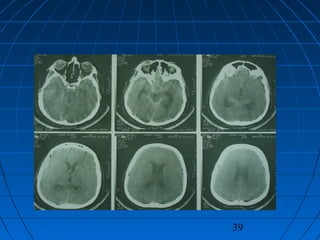

MASİF SPONTAN SAK + ICH + İVH + SDH…MASİF SPONTAN SAK + ICH + İVH + SDH…

MASİF SPONTAN SAK + ICH + İVH +…MASİF SPONTAN SAK + ICH + İVH +…

• 58 yaşında bayan hasta58 yaşında bayan hasta

• Ani bilinç kaybı şikayetiyle acilAni bilinç kaybı şikayetiyle acil

polikliniğe getirildipolikliniğe getirildi

• İlk NM:İlk NM: Bilinç kapalı; GKS: 5Bilinç kapalı; GKS: 5

Pupillalar anizokorikPupillalar anizokorik

YBÜYBÜ

5. günde exitus5. günde exitus